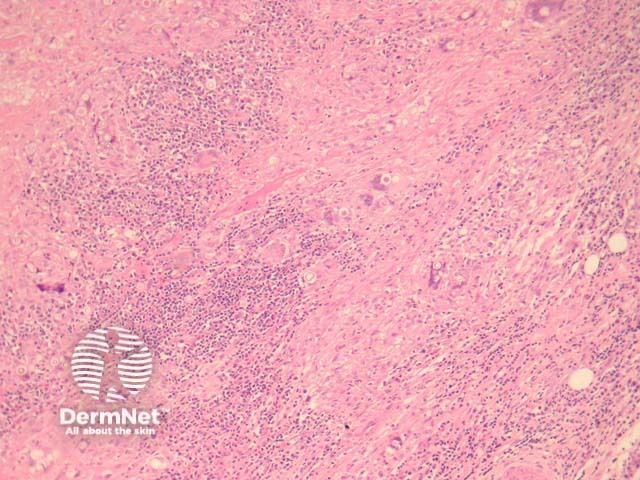

The dermis shows an acute inflammatory and granulomatous reaction pattern (figure 1). The granulomas are quite well formed and may be surrounded by a dense fibroplasia. Even at low power, numerous fungi can be seen within giant cells and surrounded by inflammation (figure 1). There may be overlying epidermal pseudoepitheliomatous hyperplasia.

Figure 1